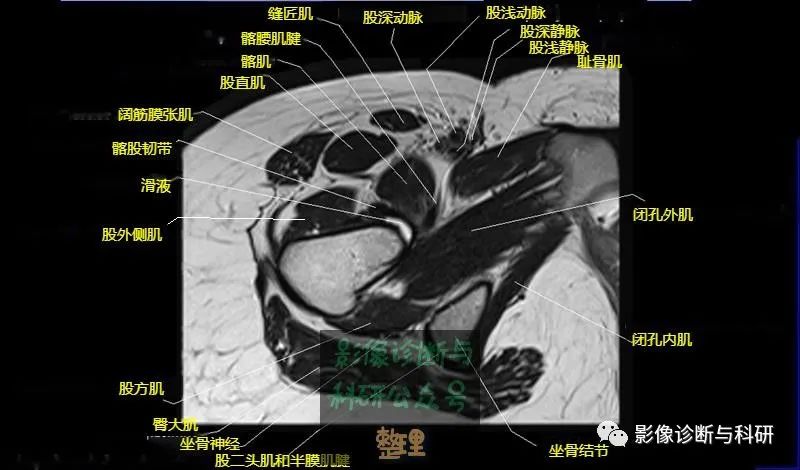

大腿肌配布于股骨周围,分前、后和内侧三群

前群

位于大腿前面,有缝匠肌和股四头肌。

作用:伸膝关节,股直肌带可屈髋关节。

内侧群

位于大腿内侧,共5块,其中股薄肌位于最内侧;另4块分三层,浅层靠外上方为为耻骨肌,下方为肌长收肌。长收肌深面是第二层的肌短收肌。第三层是强有力的大收肌。这一群肌均起自耻骨支和坐骨支,除股薄肌止于胫骨上端内侧外,其余各肌都抵止在股骨粗线。

作用:大腿内收。

后群

位于股骨后方,包括股二头肌、半腱肌和半膜肌。

作用:屈膝关节、伸髋关节。